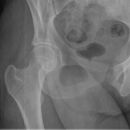

Hüfte nach Lauenstein II (15°)

Indikation

Qualitätskriterien

Gute Beurteilung des Hüftkopfes, der Pfanne und des Schenkelhalses. Der Trochanter major überdeckt bei teilweise den Schenkelhals.